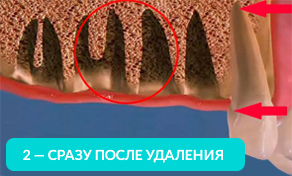

- Чем дольше Вы ходите хотя бы без одного зуба, тем больше убывает костная ткань. В 2-ух словах, для Вас это значит, что в будущем при отсутствии нескольких зубов, Вам необходимо будет либо делать дорогостоящее наращивание костной ткани, либо ставить съемные протезы (многие пациенты не соглашаются на этот вариант, но в силу дороговизны варианта с наращиванием костной ткани, им приходится ставить съемные протезы)

На рисунке видно, какие щели между зубов образуются уже через год, после удаления.

На 4-ом рисунке видно, что костная ткань стала значительно тоньше, теперь в это место уже невозможно установить импланты (потребуется операция по наращиванию костной ткани).

Обратите внимание, насколько тоньше стала кость на рисунке 4, как постепенно обнажается корень оставшегося зуба.